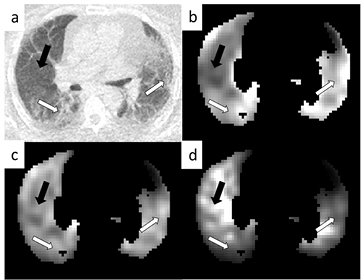

Standard image High-resolution imageFigure 3 displays an example parametric  image for each correction method. In the top left (a) the CT image can be seen displaying obvious regions of fibrosis (white arrows) and a region of normal appearing tissue (black arrow). In the top right (b) is the parametric image with no corrections displaying an apparent high influx rate in regions of fibrosis in comparison to those of normal appearance. In the bottom left (c) is the AFC image where the influx rate appears more uniform throughout the lung and after ABC (d) the regions of fibrosis appear to have a lower influx rate than those of normal appearance. Figure 4 displays the SUV results in the same layout as figure 3.

image for each correction method. In the top left (a) the CT image can be seen displaying obvious regions of fibrosis (white arrows) and a region of normal appearing tissue (black arrow). In the top right (b) is the parametric image with no corrections displaying an apparent high influx rate in regions of fibrosis in comparison to those of normal appearance. In the bottom left (c) is the AFC image where the influx rate appears more uniform throughout the lung and after ABC (d) the regions of fibrosis appear to have a lower influx rate than those of normal appearance. Figure 4 displays the SUV results in the same layout as figure 3.

Figure 3. Patlak Ki parametric images from an example patient. Image (a) is the CT displaying regions of obvious fibrosis (white arrows) and a region of normal appearing tissue (black arrow). Image (b) is the uncorrected parametric image, image (c) is the same image after AFC and image (d) after ABC. All images have been normalised such that they can be shown on the same arbitrary grey scale. All images are shown after whole lung masking with >5% fractional parenchyma volume thresholding.